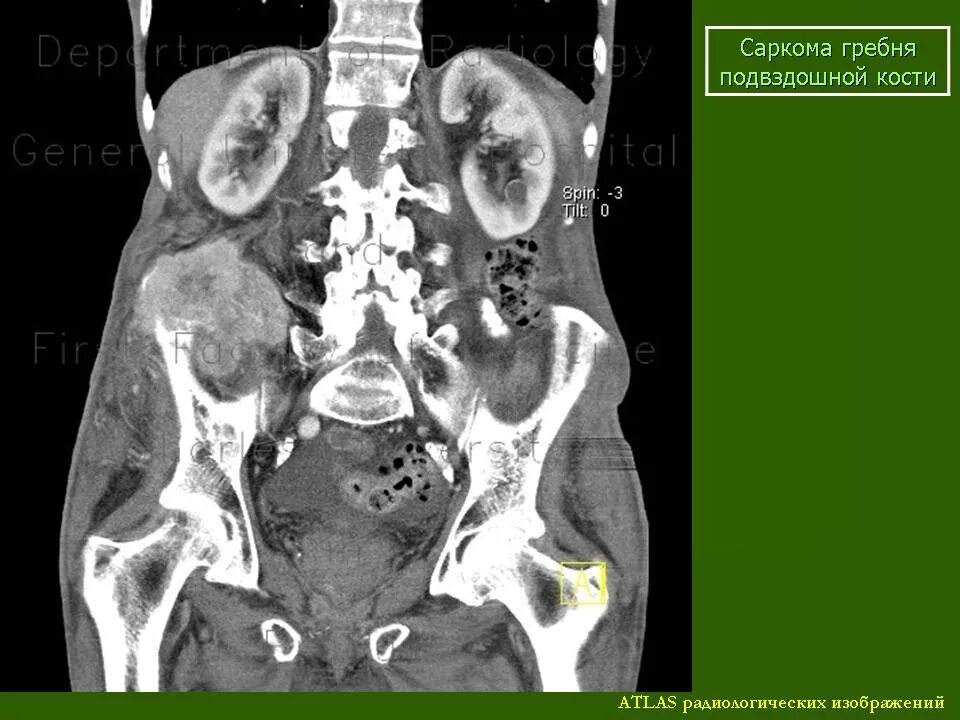

Метастазы костей мрт